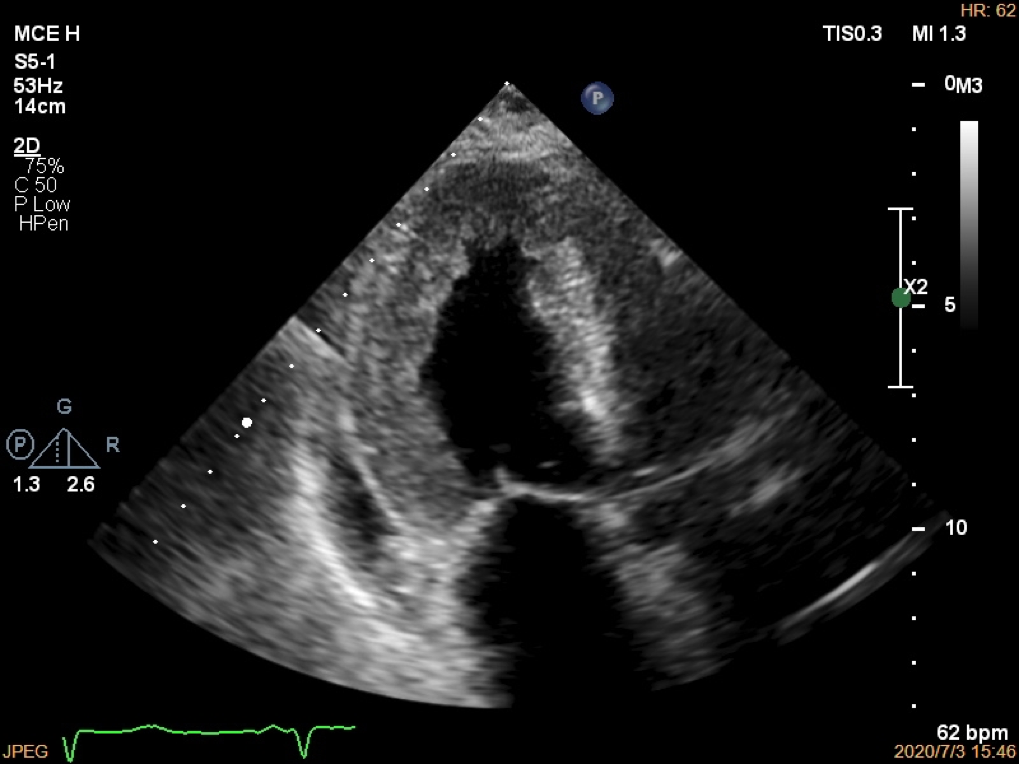

病历摘要

· 患者,女68岁,因间断胸闷、气短4月入院(2020.07.01)

2020.01.01 Holter反复窦停(6.7s),病态窦房结综合征

2020.01.06 双腔起搏器植入术

2020.03 胸闷气短、咳白痰,夜间加重,双下肢水肿